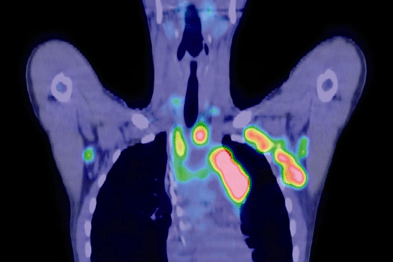

Non Hodgkins Lymphoma Symptoms

Non Hodgkins Lymphoma Symptoms Photos

Non Hodgkins Lymphoma Symptoms Pictures

Photos of Non Hodgkins Lymphoma Symptoms

Non Hodgkins Lymphoma Symptoms Images

Images of Non Hodgkins Lymphoma Symptoms

Pictures of Non Hodgkins Lymphoma Symptoms